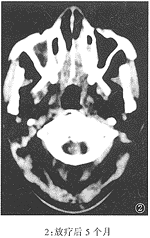

本组病例经随访观察3月~35月,平均17月(中位数15月)。除2例再粘连外,均取得了良好的通气效果。该组的CT显示:鼻腔粘连的部位多在鼻腔后份,表现为鼻甲与鼻中隔之间的空隙消失,为条索状致密阴影所填充,往往可在多个层面特别是在鼻腔的上部层面上可以观察到。治疗前后鼻甲与鼻中隔间的空隙恢复见图1、2、3。

附图 鼻腔粘连前后及手术治疗后的鼻腔CT表现

临床诊断鼻腔粘连不难,凡NPC放疗后有持续性鼻塞并伴流涕、嗅觉减退或丧失者,经鼻镜检查发现下、中鼻甲与鼻中隔相贴,用血管收缩剂不能分开,探针不能通过,粘连即可确诊。通过对经治疗的28例鼻腔粘连病例的鼻咽轴位CT的观察,发现鼻腔粘连的轴位CT有以下特点:鼻甲与鼻中隔之间的空隙消失,被条索状致密影代替;这条索状致密影往往可在多个层面特别是在鼻腔顶部的层面上观察到,而肿胀的鼻甲组织的密度较为均匀且以鼻腔下部为主,可以与因放疗引起的鼻腔粘膜肿胀及鼻腔分泌物相区别。与粘连前的CT片比较,也有助于CT上对该病的诊断。